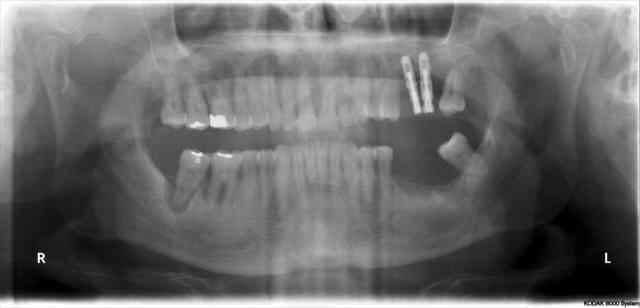

Pour être précis je dirais que l'implant en 27 et non pas 26 n'a jamais été vraiment bien

Simple question, pourquoi conserver les dents postérieures (28-38, je pense) qui sont en phase finale de paro ?

L'implant 27 devrait aussi être remplacé, enfin, selon ce qu'on voit sur les images montrées.

Il y avait 9 implants avant la chir 1 va mal et tous vous focalisé, amusant mais classique

28 n'est pas en rapport avec le problème de l'implant 27

Dans 3 mois 28 & 38 vont disparaitre, et je tenterais en même temps de sauver 27

En cas d'échec probable dans l'implant disparaitra et lors de la prothèse définitive j’intégrerais 26 ou pas